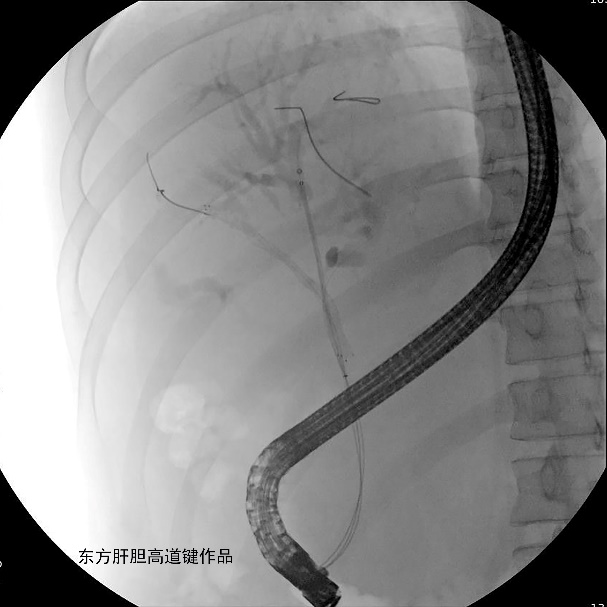

图C:第三根导丝超选进入左外侧肝内胆管;

图D:柱状气囊充分扩张胆管狭窄段;

图E:2根Zilver 8-80mm金属支架分别沿导丝插入右前与左内侧肝内胆管,完全释放右前肝内胆管的金属支架;